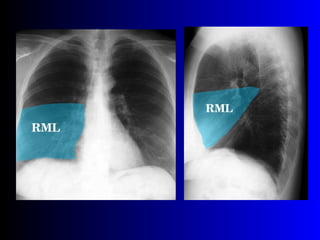

Este documento describe la técnica para realizar una telerradiografía de tórax normal e identifica las estructuras visibles en la imagen, incluyendo los huesos, vasos sanguíneos, grasa, tejido subcutáneo, pulmones y mediastino. Explica que es importante centrar la imagen en los ápices pulmonares, senos costodiafragmáticos e inspiración profunda para una visión clara de las estructuras.